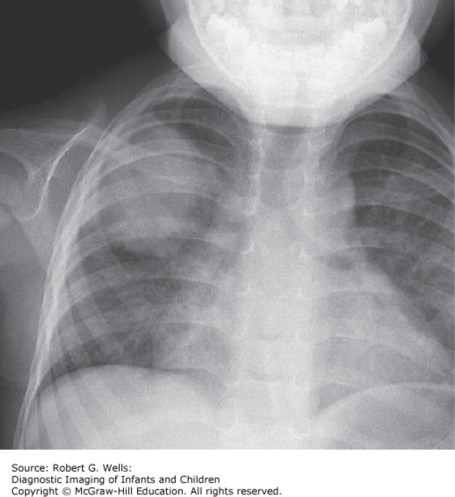

Round pneumonia. There is a round focus of dense consolidation in the right upper lobe of this febrile 14-month-old infant with pneumococcal pneumonia.

Source: Wells RG. Diagnostic Imaging of Infants and Children; 2015.